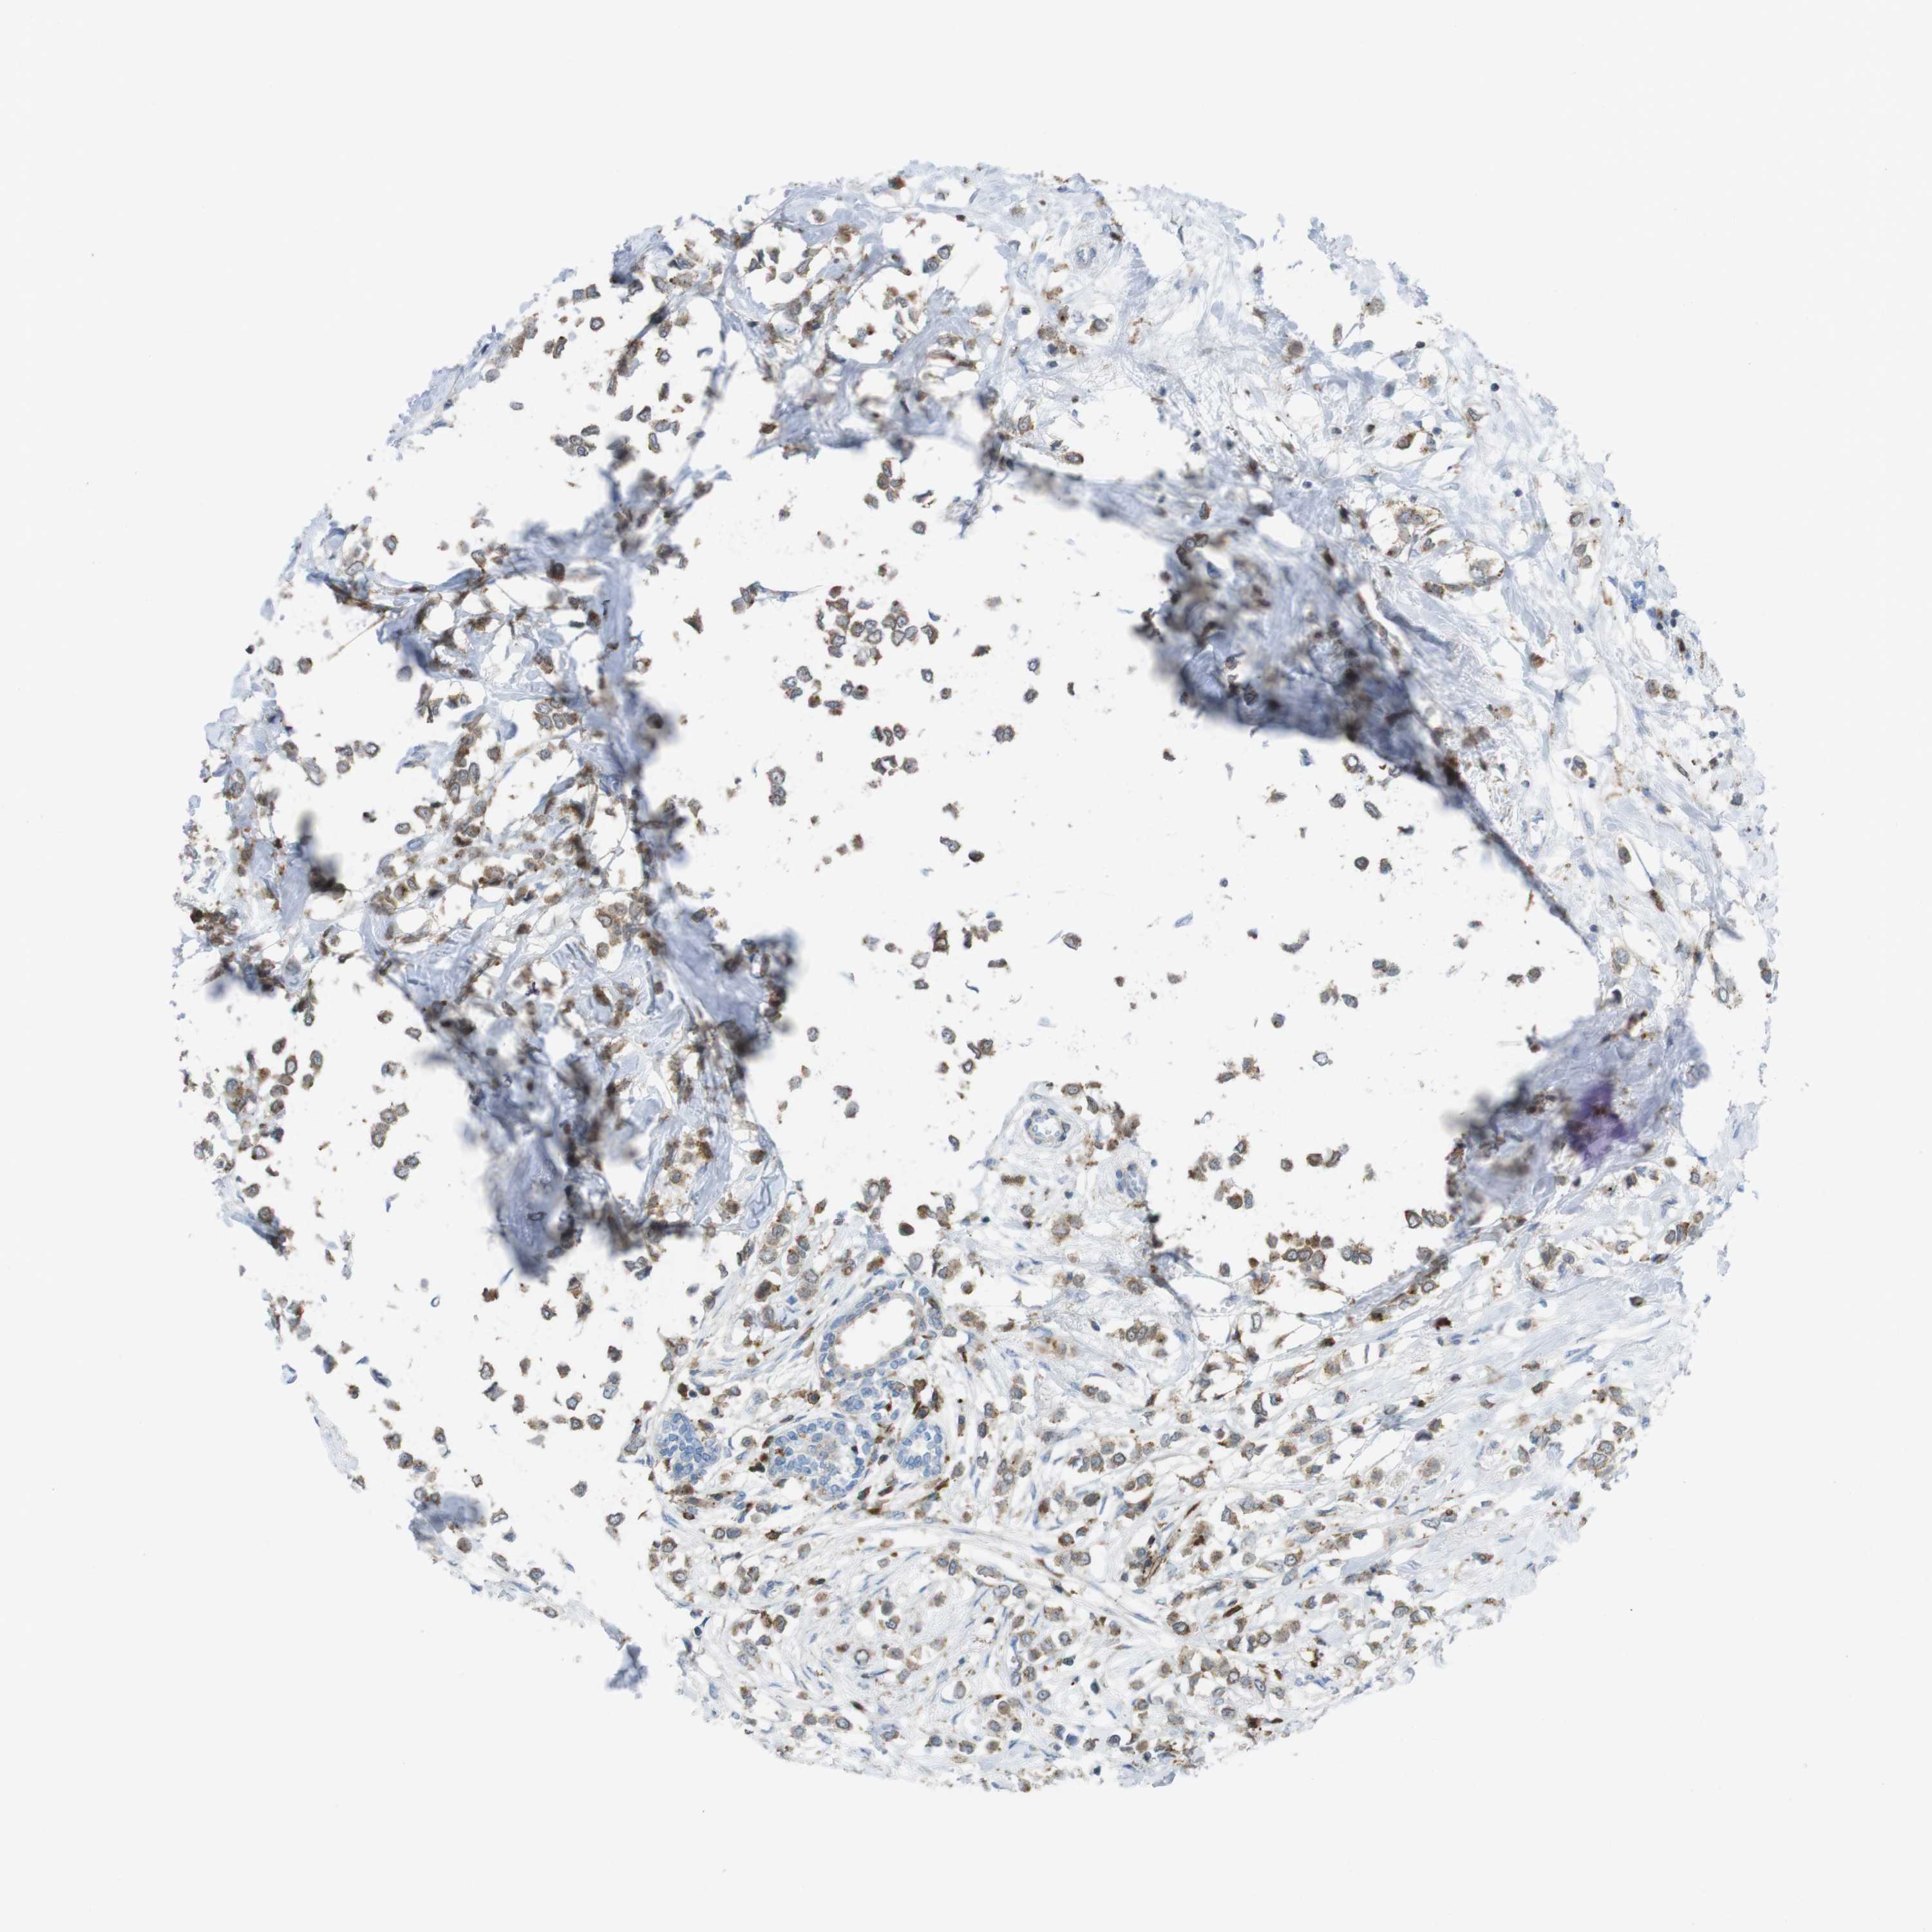

CANCER BREAST CANCER Show tissue menu

BRCA TCGA BRCA VALIDATION PROTEIN EXPRESSION